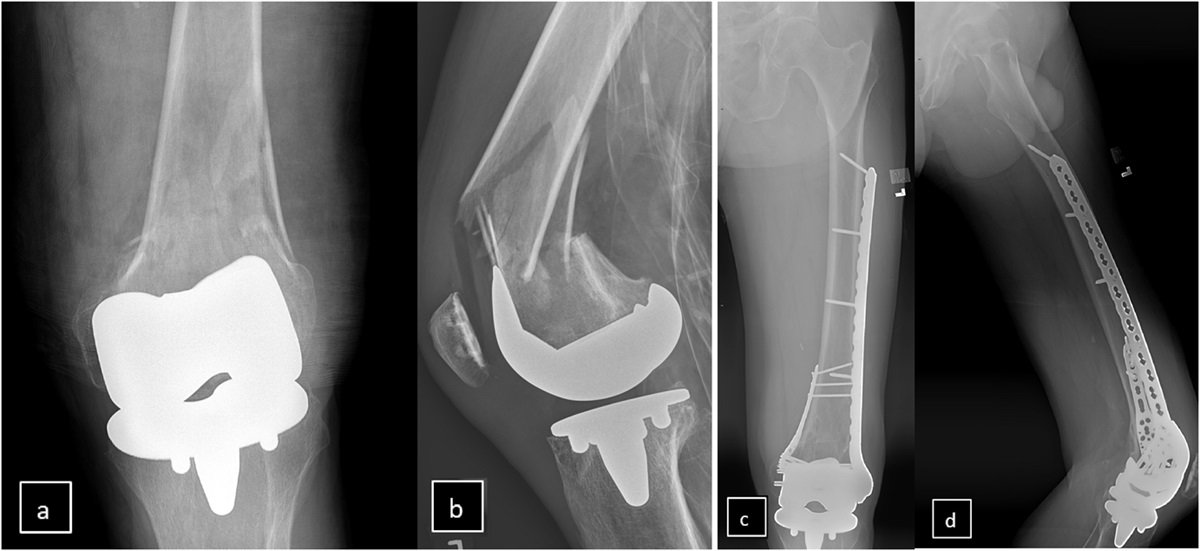

Patients who sustained an acetabular fracture and had fixation through a Kocher-Langenbeck approach from January 1st, 2008 to December 31st, 2018. For inclusion, patients had to have a pre-operative and a post-operative CT of the pelvis and a minimum follow up of 12 months. Patients were excluded if an antibiotic other than cefazolin was administered for prophylaxis, if they had a femur fracture treated with an antegrade intramedullary nail, if there was any associated pelvic ring injury requiring surgical treatment of any type, if there were any abdominal or pelvic procedures completed by another surgical service, if the patient underwent pelvic embolization of a vessel, if there was presence of a genitourinary injury or Morel-Lavallée lesion, or if there was a subsequent surgical procedure unrelated to the primary endpoint (e.g., revision fixation).